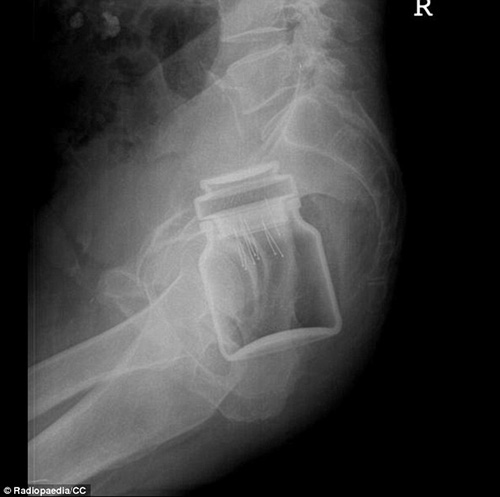

VBF- Đây là các hình ảnh được cung câp bởi các bã sĩ trong bệnh viện. Các bênh nhân sau khi để lọt các đồ vật vào người đã phải đi cấp cứu tại bệnh viện và đã được chụp X-quang để xác định đồ vật đó.Đó thường là những "vật dụng bất bình thường" được các bác sĩ khắp thế giới tìm thấy bên trong trực tràng của các bệnh nhân và chia sẻ trên trang Radiopaedia, một website giáo dục và thảo luận do các sinh viên X-quang thành lập từ năm 2005. Hình ảnh X-quang được chia sẻ trên website là vật mẫu cho việc nghiên cứu hợp tác và là giáo cụ trực quan trong giảng dạy ngành học quang quyến (môn học X-quang), hoặc dùng làm tài liệu cho các bảo tàng, đồng thời là những ví dụ giúp mọi người cảnh giác. hiếc chày trong trực tràng người đàn ông 40 tuổi được "khổ chủ" giải thích khi nấu món ăn Malaysia đã bị trượt vào trong??? Một chai đựng cà phê với những chiếc ghim gắm vào lớp cao su phía dưới nắp được bệnh nhân đưa vào trong cơ thể. Một tuýp đựng vitamin được đưa vào trong trực tràng. Thậm chí một chiếc chai cũng nằm trong danh sách bộ sưu tập các bác sĩ X-quang thu thập được. Dụng cụ rung được đưa vào qua đường hậu môn. tm tm